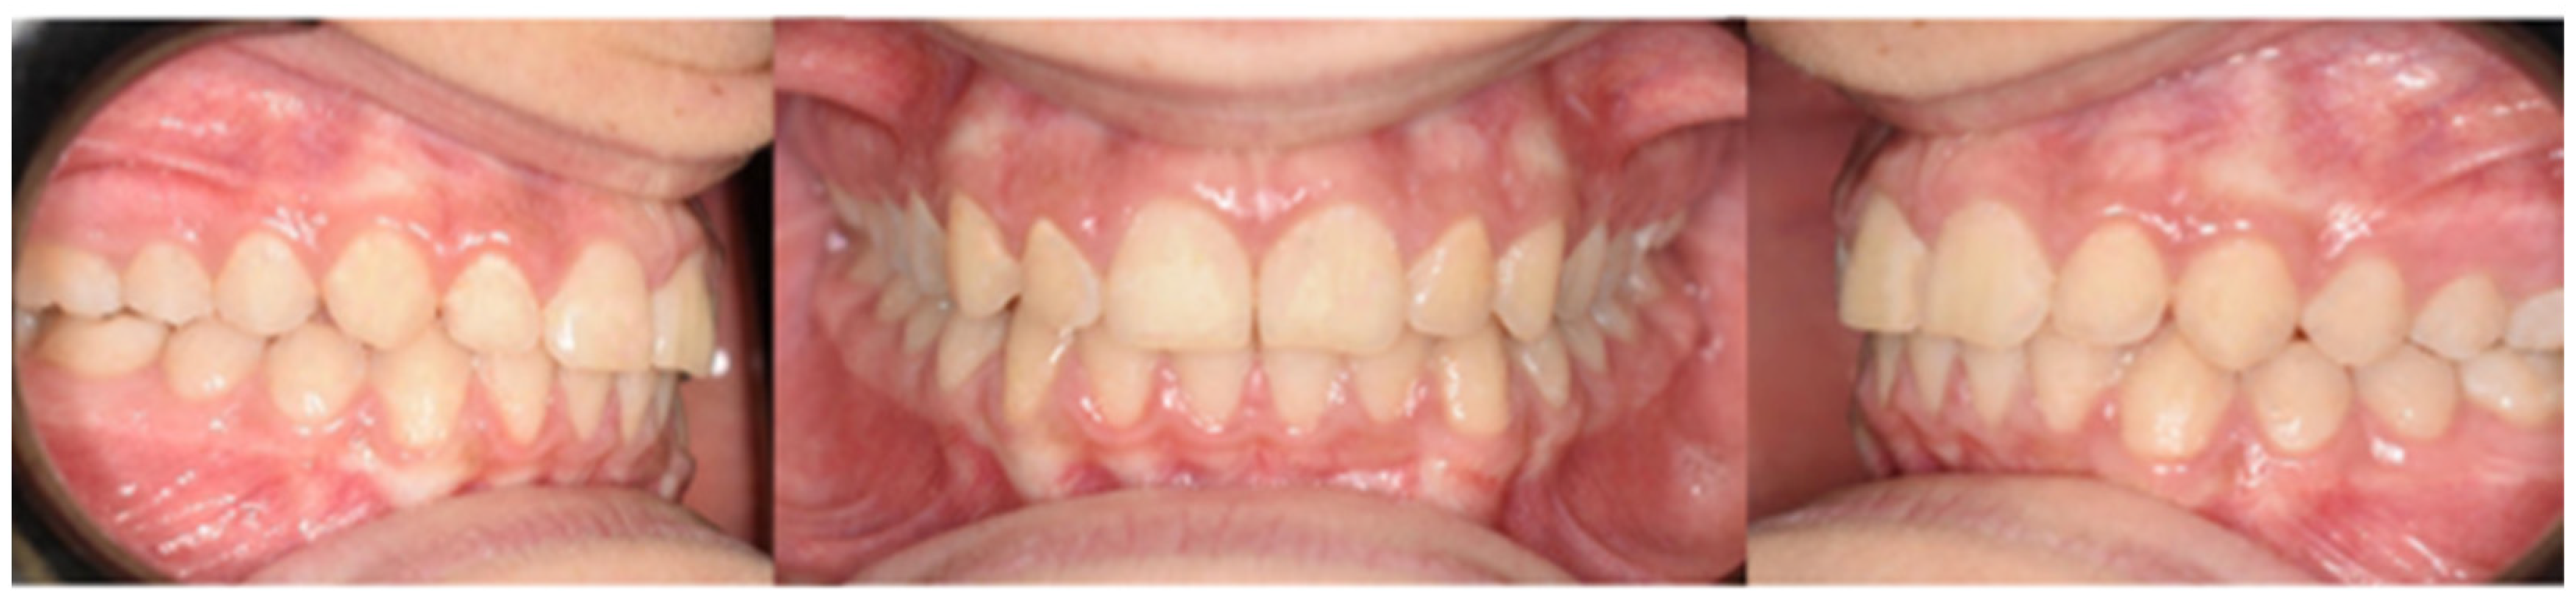

2. Presentation of Case Report

2.1. Treatment Objectives

- Improve overjet and overbite;

- Achieve bilateral canine and molar class I occlusion;

- Increase facial esthetic balance;

- Level the arches and make both coordinate with each other;

- Orthodontic correction of the impacted lower left canine.